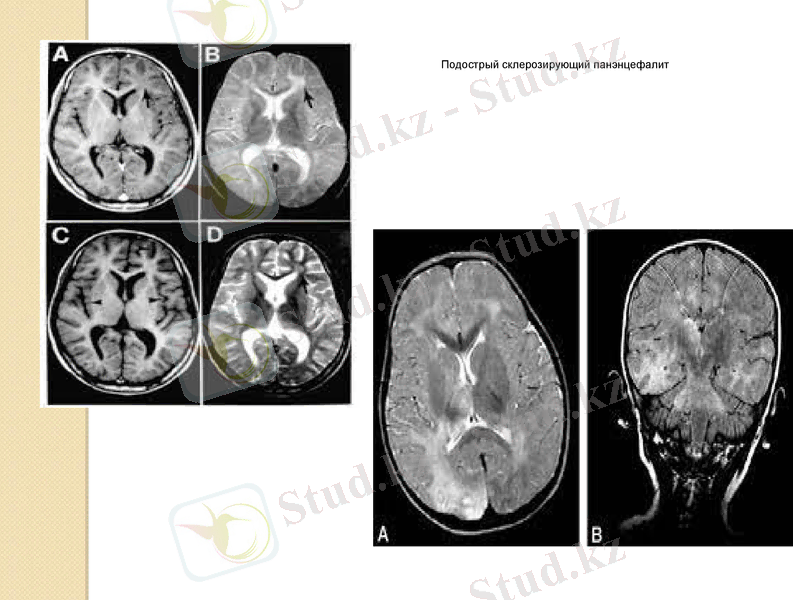

Диагноз мидың МРТ, ЭЭГ, қан және цереброспинальды сұйықтықты (CSF) зерттеу нәтижелерімен расталады. ЭЭГ-де анықталады жоғары амплитудалық мерзімді баяу миоклониямен синхрондалған толқындар. ОАОО-ДА қалыпты шектерде цитоз. Қандағы гаммаглобулин деңгейі жоғарылайды. Қанда және CSF титрлері жоғарылайды қызылша вирусына антиденелер. КТ және МРТ байқалады субкортикальды және перивентрикулярлы ақ заттағы бірнеше гиподенсивті ошақтар, а сондай-ақ базальды ганглия проекциясында. Біз 18 жастағы науқаста аурудың дебютіне клиникалық мысал келтіреміз.

Науқас М., 2011 жылдың мамырынан бастап, олар пайда болған кезде ауырады тітіркену, шаршаудың жоғарылауы, жиі көңіл-күйдің өзгеруі, мезгіл-мезгіл бас ауруы. Туыстары баяулауды байқай бастады күнделікті қозғалыстар, мінез-құлықтың өзгеруі (болды тұйық, үнсіз, мезгіл-мезгіл жыпылықтайды ашу) . МРТ-ға емхананың невропатологы жіберген миы. Өндірілген мидың МРТ в / в контраст томовиста 10 мл-Т1-Т2-өлшенген режимдерде осьтік, коронарлық, сагиттальды жазықтықта жасалған томограммалар сериясында суреттер мен FLAIR, париетальды ақ затта лобтар бүйірлік қарыншалардың артқы мүйіздері аймағында перивентрикулярлы түрде жоғарылаған ошақтар анықталады flair және T2-өлшенген сигнал қарқындылығы оң жақ париетальды лобтағы өлшемі 14 дана 10 мм кескіндер. Осьтік және сагиттальды жазықтықтардағы контрасттан кейінгі Т1-өлшенген кескіндерде контрастты заттың патологиялық жинақталуы мидың паренхимасында және қабықшаларында анықталмайды. В қалған бөлімдерде 08. 07. 2011 ж. бастап 11. 07. 2011 ж. дейін неврологиялық бөлімшеде стационарлық емделуде болды Славянск қаласындағы № 1 горболицаның диагнозы: жіті диссеминирленген энцефаломиелит, жағдайы экстрапирамидалық және пирамидалық жеткіліксіздіктің жоғарылауы түрінде біртіндеп нашарлады. "ИНВХ" ММ емханасына консультацияға жіберілді оларға. В. К. ГУСАКА НАМНУ " невропатологқа жәнергентті болды ауруханаға жатқызылды. 15. 07. 2011 бастап емделуде болды 12. 08. 2011 ж. Балалық шақта өткен аурулардың ішінде-жиі ЖРВИ, егу кестесіне сәйкес жасына қарай егілген. 15 жастағы Аппендэктомия. 1993 жылы субмандибулярлы іріңге операция жасалды лимфаденит оң жақта. Scabies 1994 ж соңғы тасымалданған ЖРВИ 13. 12. 2010 жылы жоғары температурада бір апта ішінде 39 °с дейін, медициналық көмек үшін ол ауруханаға бармады, өзін-өзі емдеді (яғни. осы аурудан 5 ай бұрын) . ТБС, іш сүзегі, безгек, жыныстық жолмен берілетін аурулар, Боткин ауруы, қан құюды жоққа шығарады.

Подострый склерозирующий панэнцефалит

УДДГ 27. 07. 2011 ж. - ПА бойынша қан ағымының асимметриясы D < S 40 %, оң жақта перфузия қиын. Ми тамырларының гипоперфузиясы сол жақта көбірек, негізгі артериялар. Диастола кезінде ретроградтық құю VSA (мүмкін кардиогендік сипатта) . Дерматолог-себореялық дерматит. Мидың қайта МРТ 28. 07. 2011 ж (сурет. 1) . Мидың МРТ сериясында осьтік және сагиттальды проекцияда режимдерде T1-T2-өлшенген кескіндер және FAST FLAIR сол жақтағы самай-оксипитопариальды аймақта субкортикальды және кортикальды кең аймақ анықталады шамамен аймақ өлшемдері 78 35 тарау 65 мм, бұлыңғыр біркелкі емес режимде жоғары МР-сигналы бар контурлар T2-VI және FAST FLAIR, T1-VI режимінде Орташа Төмен Мрсигналмен, орташа қысумен іргелес субарахноидты кеңістіктер. Ортаңғы құрылымдар біржақты емес, бас қарыншалары ми кеңеймеген, бүйір қарыншалардың денелері асимметриялы, бүйір қарыншалардың өлшемдері: алдыңғы мүйіздер-4, 5 мм, денелер оң жақта-7, 5 мм, сол жақта-10 мм, үшінші қарынша - 3 мм-ге дейін. цистерналардың кеңеюі анықталады: базальды, параселлярлық. Субарахноидты кеңістіктердің кеңеюі анықталады екі жағынан фронтальды-париетальды аймақтарда.